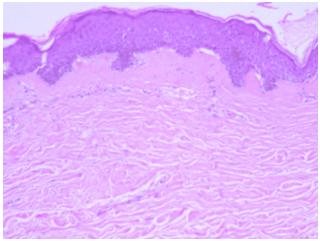

La enfermedad relacionada con la inmunoglobulina G4 (IgG4), conocida como "IgG4-related disease" en inglés, es un trastorno sistémico de causa desconocida que se caracteriza por una fibroinflamación altamente característica. Esta…